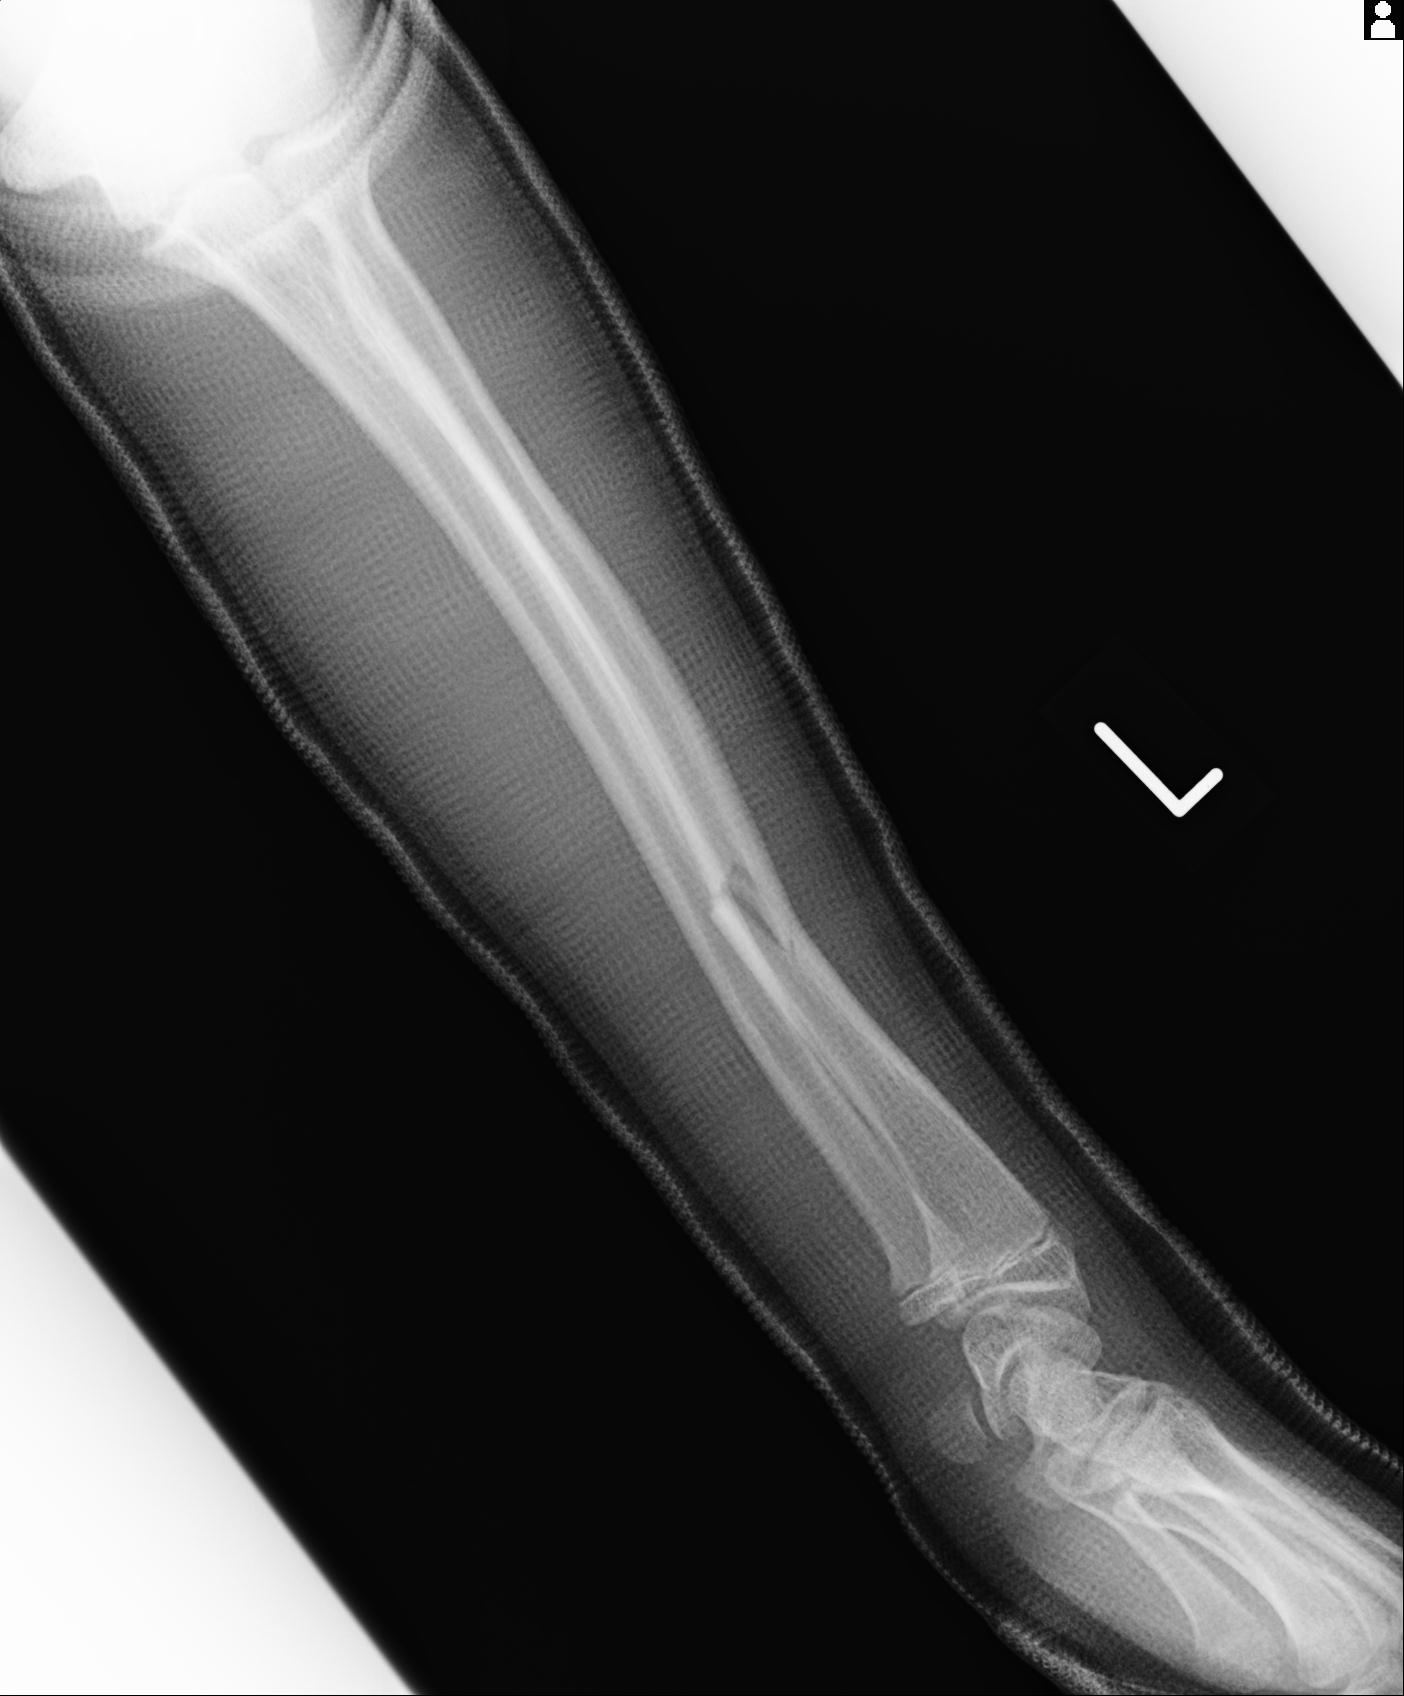

110211 1/6 1/8 左前腕 4R 15歳男性 橈骨骨幹部骨折